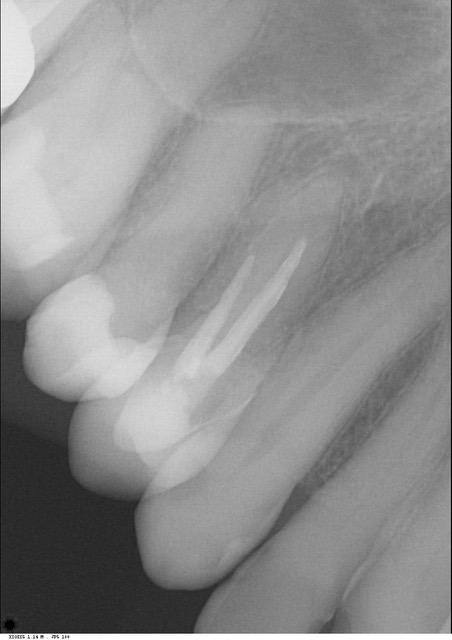

Kunt u bitewing foto's plaatsen van de "gezonde" kant en van de linker onderkant ?

Ik heb nog een aantal afbeeldingen van de scan online gezet, en een overzichtsfoto, die een paar maanden na de WKB is gemaakt. >>http://3dscan.jalbum.net/x-ray-scan/<<

Daarmee is ze naar de kaakchirurg geweest omdat de tandarts dacht aan een kaakholte ontsteking. Hoe dit verder is verlopen moet ik ook even op een rijtje zetten.

de foto's zijn van okt/nov 2020 en de cbct van juni 2021.

Welke kroon is als laatste geplaatst?. Als het de 16 is dan zou ik op basis v d tweede foto zien dat aan een v d mesiale ( voorste wortel) een ontsteking is. Excuseer als ik het fout zie, ik moet het doen met wat u mij levert. Wortelpunt v d 14 is voor mij ook verdacht. Koud en warm alleen in die kies of meerdere, dat is verwarrend maar kan verklaard worden doordat een kanaal "dood" is en de andere nog niet. Ik zou in de 16 proefboren zonder verdoving. Als er geen gevoel in is dan een wortelkanaal behandeling. Maar als er toch gevoel in zit geeft dat geen uitsluitsel. Ik zou beginnen met een WKB in de 16. U bent overal geweest zegt u. Wat was het oordeel v d endodontoloog.